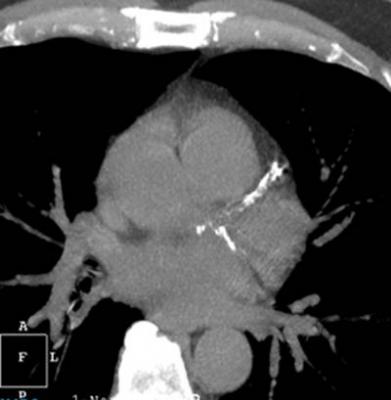

December 28, 2017 — HeartFlow Inc. announced that Health Care Service Corp. (HCSC), which operates Blue Cross and Blue Shield plans in five states, has issued a medical policy for the HeartFlow FFRct Analysis, a non-invasive technology that helps clinicians diagnose and treat patients with suspected coronary artery disease (CAD). HCSC — which operates Blue Cross Blue Shield plans in Illinois, Montana, New Mexico, Oklahoma and Texas — has determined that the use of noninvasive fractional flow reserve (FFR) following a positive coronary computed tomography (CT) angiogram may be considered medically necessary to guide decisions about the use of invasive coronary angiography in patients with stable chest pain at intermediate risk of CAD.

The Centers for Medicare & Medicaid Services (CMS) and a growing number of commercial payers and professional organizations have recognized the value of the HeartFlow FFRct Analysis in diagnosing patients with suspected CAD, according to the company. CMS finalized a New Technology Ambulatory Payment Classification (APC) for the HeartFlow FFRct Analysis in November. Beginning Jan. 1, 2018, hospitals that are enrolled in Medicare and bill CMS will be able to submit claims for the HeartFlow FFRct Analysis for Medicare patients.